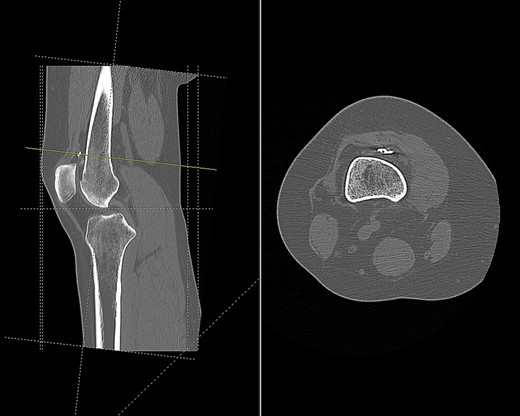

CT (Fig. 1) and MR imaging showed an endobutton and endocord sitting superior to the patella, with both impinging upon the articular surface of the medial patella facet. A metal susceptibility artefact was seen at the medial femoral condyle, which was identified as an interference screw.

CT scan of the right knee showing the endobutton in suprapatellar pouch (sagittal and axial view).